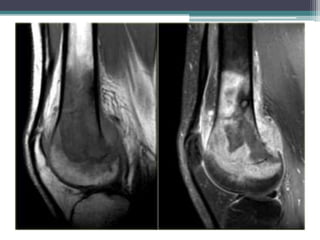

• El crecimiento de los osteocondromas en edades adultas

(caracterizada por una gruesa capa cartilaginosa

observado como SI alta ponderado en T2 de RM); debe

plantear la sospecha de progresión a un condrosarcoma.